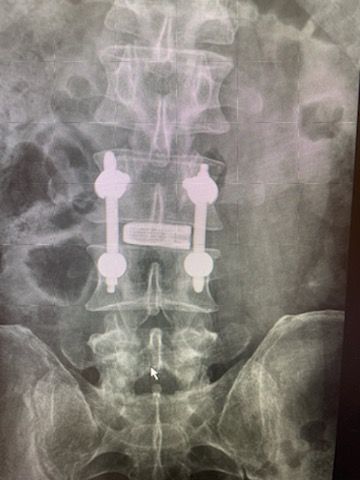

Starszy Asystent w Klinicznym Oddziale Neurochirurgicznym oraz Poradni Neurochirurgii Wojewódzkiego Szpitala Specjalistycznego im. św. Barbary nr 5 w Sosnowcu. Konsultant Kliniki Neurologii Szpitala Klinicznego nr 1 w Zabrzu. Absolwent Wydziału Lekarskiego Śląskiego Uniwersytetu Medycznego w Zabrzu. Staż podyplomowy odbył w latach 2010-2011 w Oddziale Neurochirurgii WSS nr 4 w Bytomiu. W 2018r. złożył egzamin specjalizacyjny po zakończeniu szkolenia w ramach rezydentury w WCM Opole. W 2019 roku uzyskał stopień doktora nauk medycznych. Specjalizuje się w kompleksowym leczeniu schorzeń kręgosłupa (dyskopatia, stenoza kanału kręgowego, kręgozmyk) oraz neuroonkologii. Szczególny zakres działań medycznych to nowoczesne, małoinwazyjne operacje kręgosłupa z wykorzystaniem technik endoskopowych (mikrodiscektomia - implanty rozprężalne), przezskórnych stabilizacji oraz mikrochirurgicznych dekompresji. Wykonuje procedury iniekcyjne; discoGEL, GelSTIX, kriolezje oraz blokady przeciwbólowe kręgosłupa odcinka szyjnego, lędźwiowo-krzyżowego a także stawów krzyżowo-biodrowych, które odgrywają istotną rolę w procesie diagnostyczno-leczniczym wielu zespołów bólowych. Na co dzień przeprowadza operacje w ramach kontraktu z NFZ. Członek Polskiego Towarzystwa Neurochirurgów oraz Polskiego Towarzystwa Chirurgii Kręgosłupa. Uczestnik wielu krajowych i zagranicznych kursów neurochirurgicznych, m.in. w Czechach, Słowacji, Niemczech, Włoszech, Danii, Austrii, Szwajcarii i USA. Autor licznych publikacji naukowych.

Zdjęcia i filmy